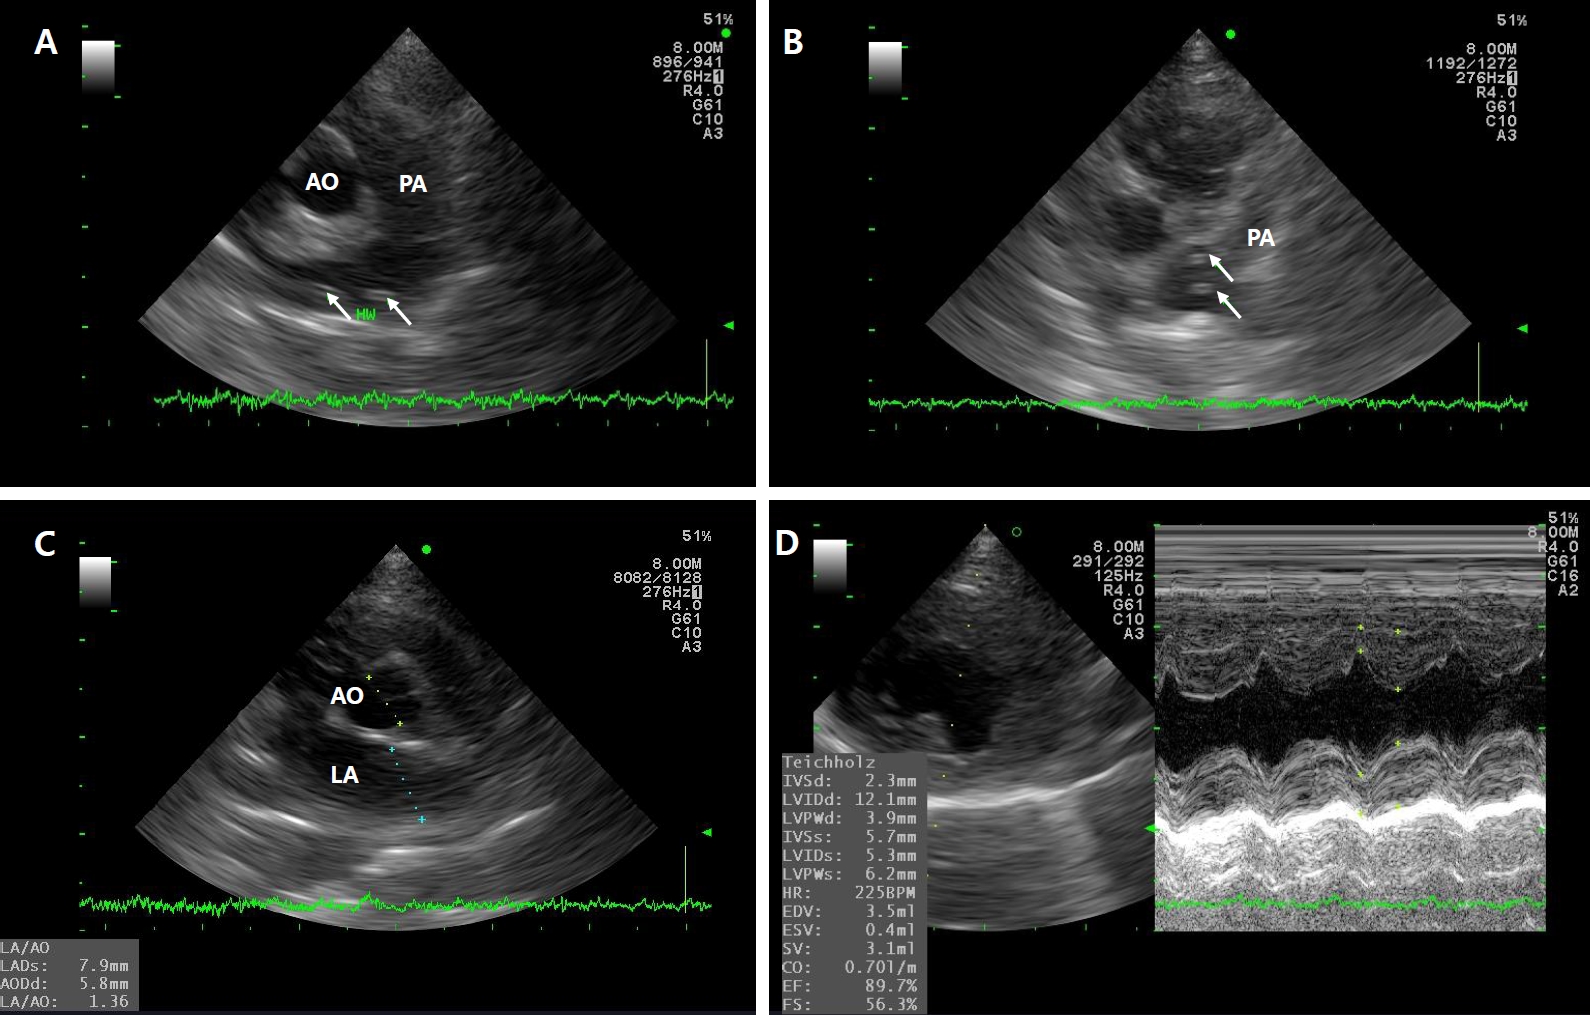

A 5-year-old rescued female stray cat presented with generalized skin ulcers, maggot infestation, and cachexia in August 2019. CBC, serum chemistry, electrolyte analysis, proBNP, FeLV and FIV tests, heartworm antigen and antibody kit tests, thoracic and abdominal radiographs, and abdominal ultrasound were performed. Test results were positive for heartworm antigen and antibody tests, anemia, dehydration, and azotemia. Thoracic radiographs revealed marked dilation and tortuosity of pulmonary arteries coursing through both caudal lung lobes. B-mode echocardiography revealed multiple hyperechoic, parallel double lines within the main pulmonary artery bifurcation and right pulmonary artery branches, consistent with adult heartworms. Standard short-axis, M-mode, and Doppler echocardiography demonstrated a normal left atrium-to-aorta ratio (1.36), preserved systolic function (fractional shortening: 56.3%), and no evidence of severe pulmonary hypertension. These findings confirmed the presence of multiple adult heartworms (

Fig. 2).

20]. With appropriate management, the cat has survived for 4 years following diagnosis and has remained asymptomatic to date. In Case 2, echocardiography played a pivotal role in confirming heartworm infection in this cat, demonstrating characteristic imaging findings. B-mode imaging revealed multiple hyperechoic, parallel double lines in the main and right pulmonary arteries, a pathognomonic sign of adult heartworms. Echocardiography showed normal chamber sizes, preserved systolic function, and no severe pulmonary hypertension, underscoring its value for detecting early or asymptomatic infections and complementing antigen testing.

Fig. 2.Echocardiographic findings in Case 2. (A, B) B-mode image showing multiple hyperechoic, parallel double lines (white arrows) within the bifurcation of the main pulmonary artery (PA) and branches of the right PA, consistent with intraluminal adult heartworms. (C) Right parasternal short-axis view at the level of the aortic root showing a left atrium (LA)-to-aorta (AO) ratio of 1.36, indicating no overt left atrial enlargement. (D) M-mode echocardiography demonstrating normal left ventricular wall motion and systolic function (fractional shortening: 56.3%).